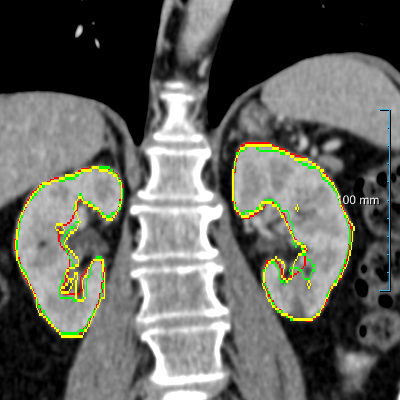

Refer to caption

(a) Patients without kidney abnormalities.

(b) Patients with kidney abnormalities.

Figure 3: Four examples of CT scans from the training set (dataset A) showing coronal sections with annotations in format 2 (see Figure 2(c)) where yellow and red overlays represent annotations of the parenchyma and kidney abnormalities, respectively. Note that all the patients have anomalies in the body (green arrows in the body), and both cases of (b) have only one kidney and contain kidney abnormalities. All the slices have a window center of 60 HU and a window width of 360 HU.

Samples of CT scans from patients included in this study can be seen in Figure 3. While Figure 3(a) depicts patients without kidney abnormalities, it highlights the presence of abnormalities in other parts of the body, such as liver tumors. Figure 3(b) shows patients with kidney abnormalities, as well as other abnormalities in the body, such as nephrectomy and collapsed lung.